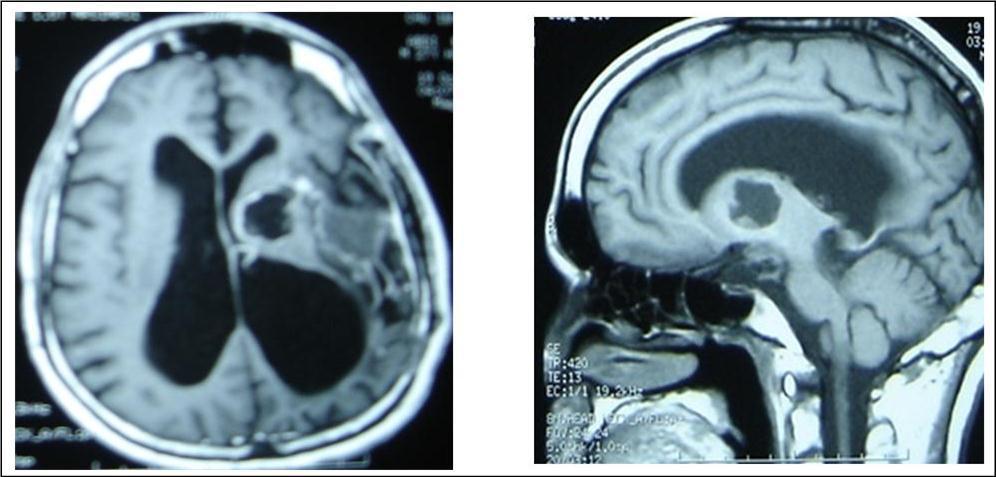

A 27 years-old male patient was admitted with 1 month history of headache, fever, short term memory lack, aphasia, right hemiparesis and seizures. He had liver hydatid cysts excised 8 years before and was treated with adjuvant medication (albendazole). The neurological examination revealed right central third cranial nerve palsy and hemi paresis, with Babinski sign positive, aphasia and papilledema on ocular fundus. The Glasgow Coma Scale was evaluated to 10/15 (E:3; V:1; M:6). A brain CT scan showed a large left temporoparietal intracerebral multiple and calcified hydatid cysts, important mass effect with midline shift about 7 mm following by an obstructive hydrocephalus (Figure 1). Other cysts were found in thalamic region (Figure 2). The Thoraco-abdominal CT scan showed multiple intra peritoneal hydatid cysts (Figure 3). A left temporo parietal craniotomy was performed in emergency. After corticectomy, using Arana-Iniguez technique, the appearance of the capsule suggested infected hydatid cysts with a purulent material which was aspirated. Numerous hydatid cysts were lifted away and several daughter vesicles were carefully removed without rupture (Figure 4). Macroscopically, the abscess wall appeared to be thick, calcified and tightly attached to lateral ventricular, so it could not be removed. The deep cyst overlying the third ventricle was left.in place. Microscopic examination demonstrated live scoleces, protoscoleces and multiple hooks. These findings are consistent with hydatid cyst (granulosis ecchinococcus) (Figure 5). Bacteriology examination found several white blood cells in the pus (neutrophilia) and infection by streptococcus pneumonia. This was consistent with infection. After surgery, the patient had medication (albendazole, specific antibiotherapy and phenobarbital). The inflammation assessment in the blood showed leukocytosis, a high C-reactive protein rate and increased erythrocyte sedimentation rate. Post operative CT scan was performed and showed the residual calcified capsule and decreased ventricular size (Figure 6). Clinical improvement was achieved after treatment. One month after the initial diagnosis, CT scan of the brain showed no recurrence and a physical examination revealed a neurologically intact, fully functional patient and eyes fundus normal. He was discharged and went to abdominal surgery two months later with complete intra abdominal cysts removal. Albendazole treatment was continuing for six months and radiological exploration was performed by brain MRI with spectroscopy at three and six month later. This showed that infection had resolved and the deep cyst overlying the third ventricle is less spherical (Figure 7, Figure 8). Four years later, the outcome was good.

Figure 7.sagittal and axial T1 C+ MRI showing the residual capsule and deep cyst.